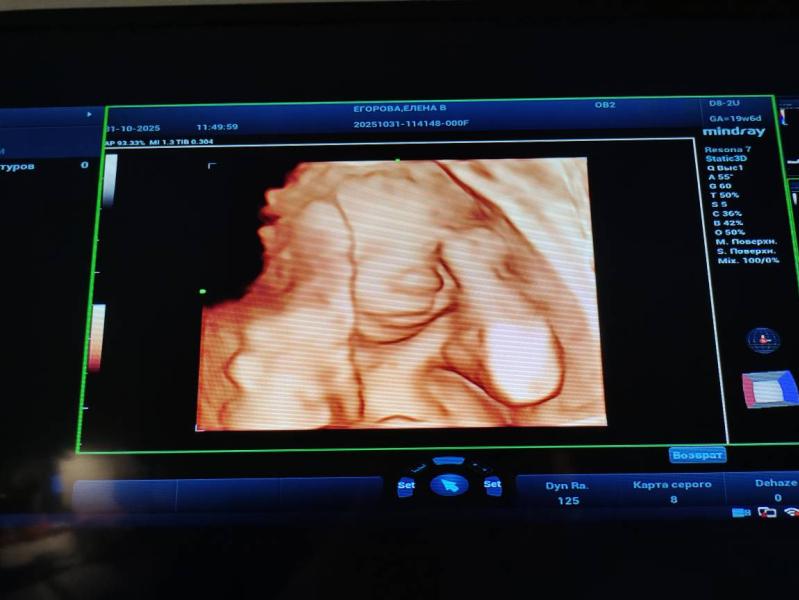

Мечта🥹❤️ я так рада😭🥹💐

@foreversmile98 у меня прям держалось чувство, что мальчик, и все вокруг были уверены, что мальчик, и я так удивилась и очень обрадовалась когда увидел, а что девочка, вот не передать🥹очень хотела вторую дочку, прям мечтала😍